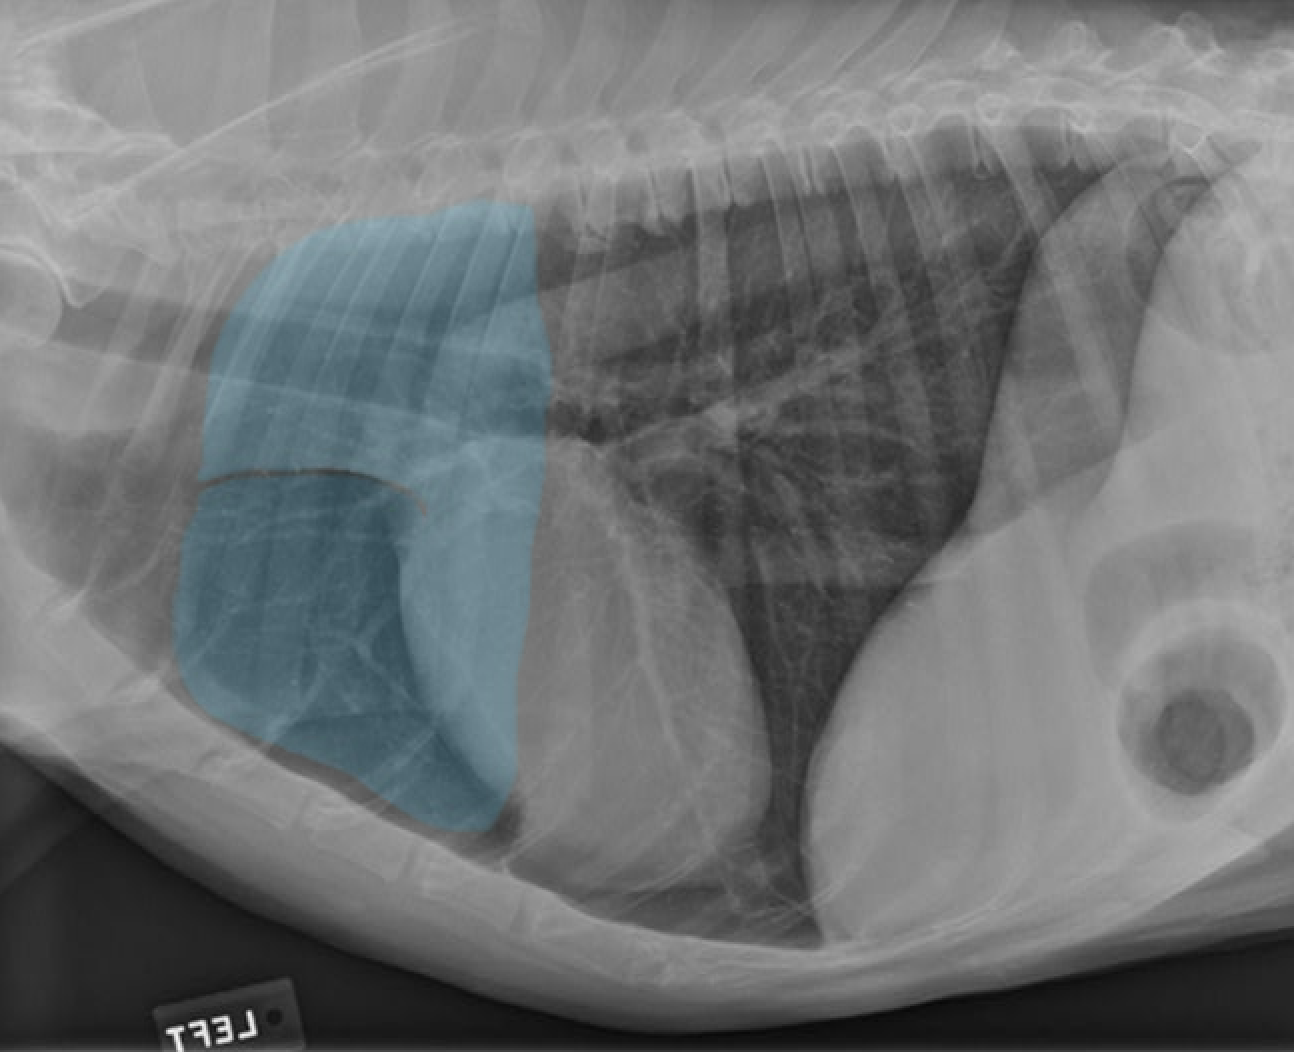

identify the structures

identify the pulomary arteries

identify the aorta

identify the ventral mediastiunum

identify the scapula

identify the ventral lung lobes